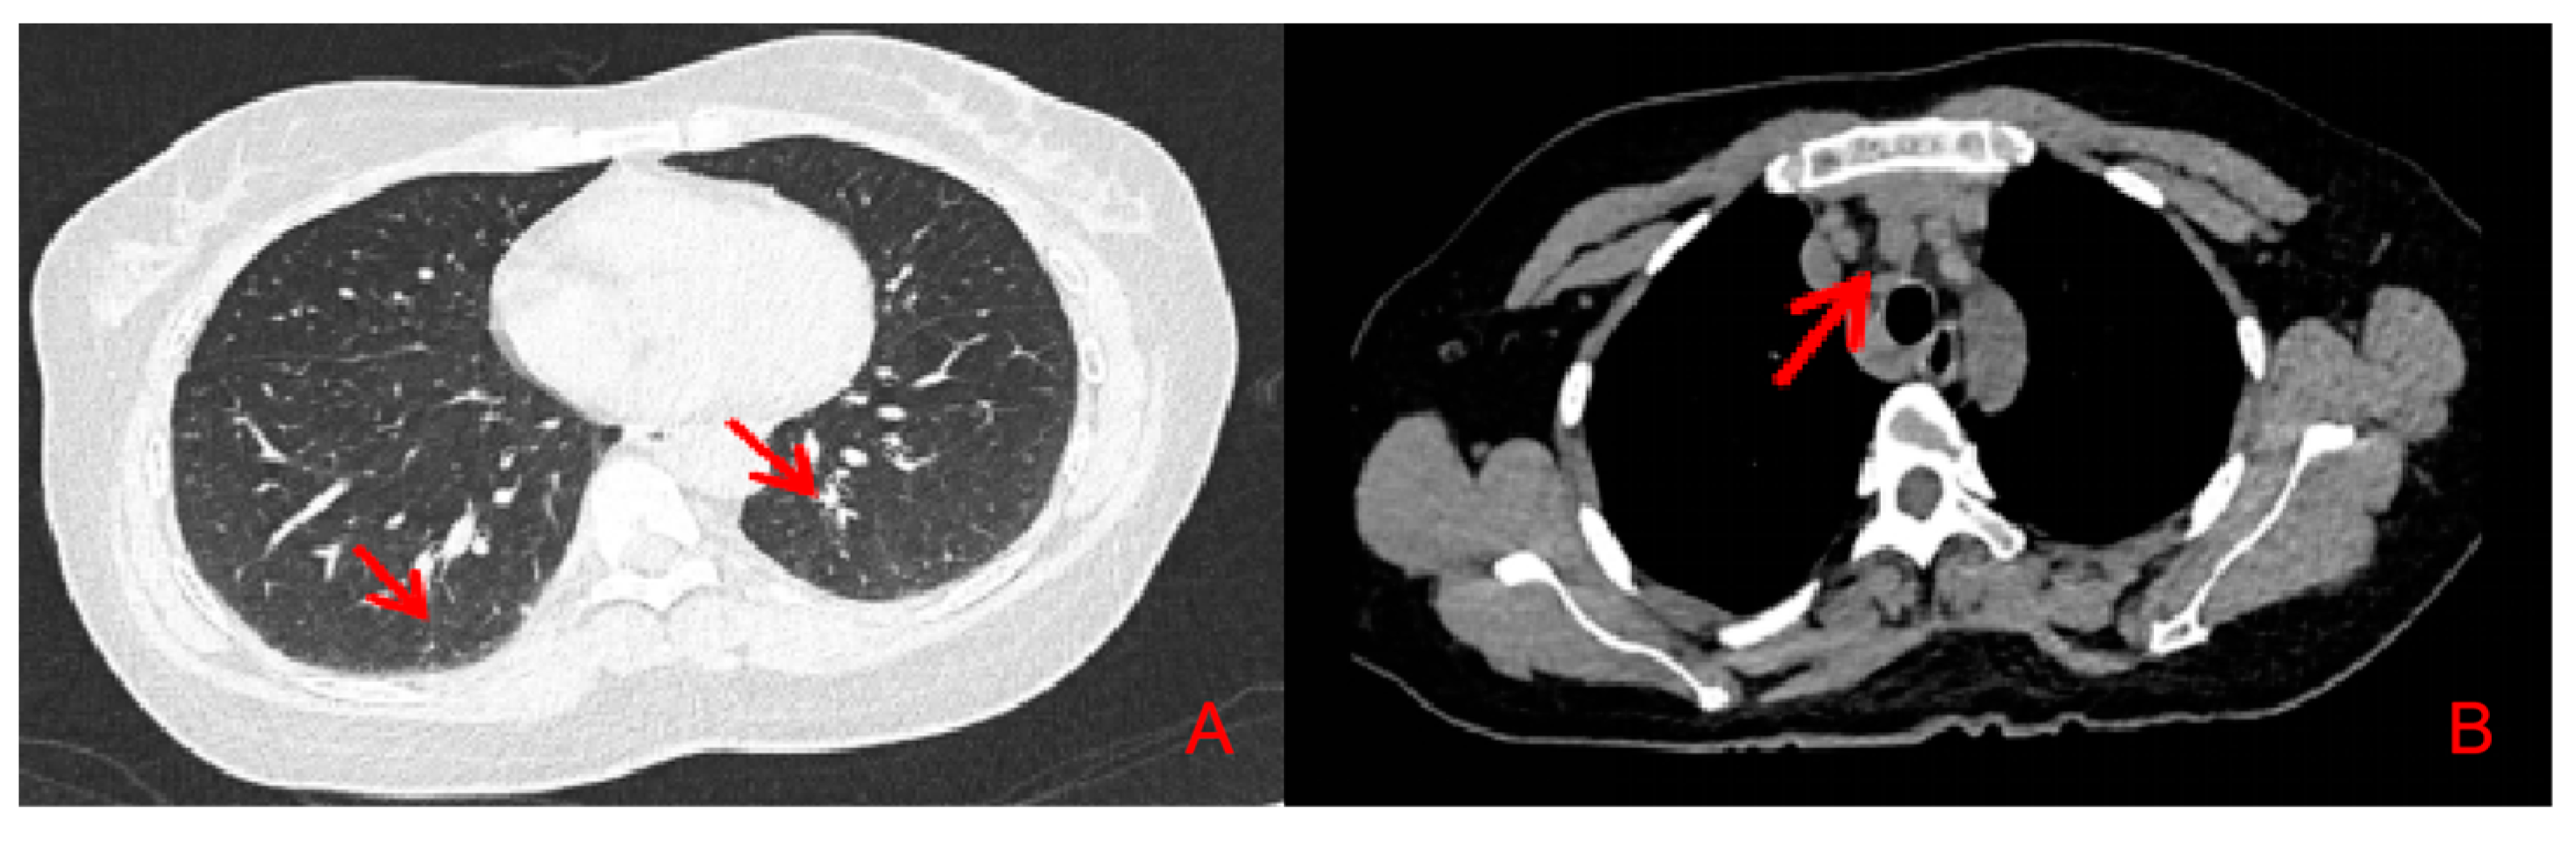

2. Case Presentation